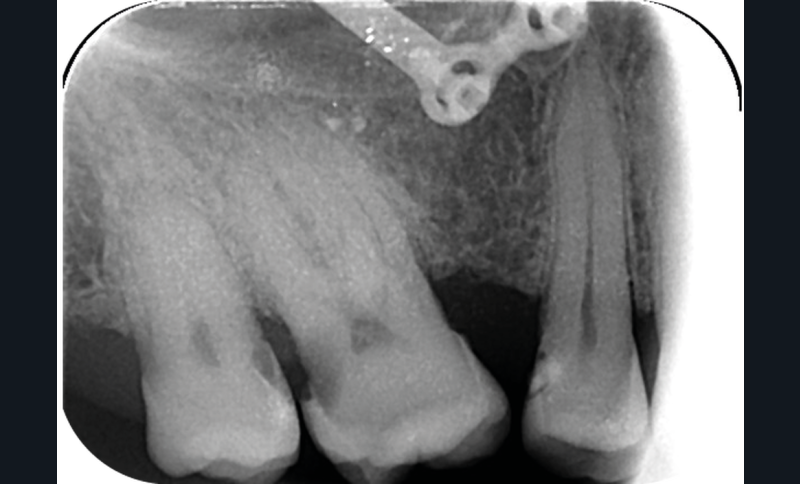

Cette version, quand elle se produit, modifie les espaces interdentaires et complique l’hygiène proximale des patients. Des caries peuvent alors se développer en interproximal sans que cela soit forcément visible à l’examen visuel (fig. 3 et 4). Les radios de type bite-wing (rétro-coronaires) prennent alors tout leur sens (fig. 5 et 6).